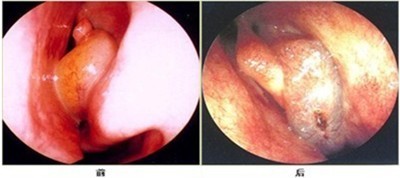

ΓΓΓΓΘ®ΆΦΈΣΘΚ±«ώΦ―ΉΜΦ’Ώ÷ΈΝΤœ÷≥ΓΘ© Θ®ΆΦΈΣΘΚ±«ώΦ―Ή÷ΈΝΤΆΦΤΉΘ©